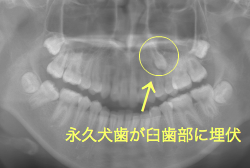

牽引(埋伏犬歯を牽引した症例)

埋伏歯とは、骨または歯茎の下に埋まって出てこない状態の歯のことを言います。埋伏歯があると歯が押されて歯並びが悪くなってしまったり、永久歯が生えてこれない原因になる恐れがあります。

埋伏歯の多くは、乳歯の早期脱落や晩期残存(乳歯が抜けずに残ること)、顎の骨の不十分な発育などにより、永久歯の生えてくる場所が不足することで生じます。また、歯が骨と癒着してしまったり、歯の形、大きさの異常など、正常な萌出を妨げる要因があると埋伏歯が生じることもあります。

「乳歯が生え替わらない」という主訴で来院したケースです。 診断の結果、「左上永久犬歯が第一小臼歯後方上部に埋伏しているため、左上乳犬歯が晩期残存している症例」と判明しました。

このような症状の場合は、手術で埋伏している永久歯に金具を取り付け、矯正装置で牽引する必要があります。同時に凸凹の解消と前突した前歯を内側に入れるために上下左右の小臼歯を抜歯させて頂くことといたしました。

この方の場合は、マルチブラケット装置にて治療を開始し、治療期間2年3ヶ月で終了しました。犬歯の牽引距離が非常に大きかったため当院の平均治療期間よりも大幅に期間がかかりましたが、埋伏犬歯を完全に正しい位置まで誘導することができました。同時に 前歯の前突と配列の凸凹も解消しました。

このような症例は、成人してしまうと埋伏歯の反応性が悪く、あまりにも動きが悪い場合は牽引をあきらめて抜歯する場合もあります。歯科医院の検診で親知らず以外の埋伏歯を指摘された場合は、できるだけ早く矯正専門医に御相談下さい。